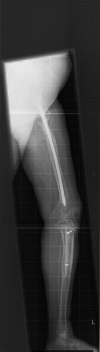

Case presentation: In this report, we describe the case of a 49-year-old Caucasian woman known for years to have fibrous dysplasia in the left femur and tibia who presented with progressive pain in her left leg and soft swelling in the left quadriceps region. After surgical intervention with excision of the soft-tissue mass, the diagnosis of Mazabraud's syndrome was confirmed. During follow-up, our patient presented with a painless mass located on the lateral side of the left knee, next to a second, intra-osseous lesion with the same characteristics in the left lateral tibial plateau. The histopathological examination was consistent with a soft-tissue intra-osseous myxoma.